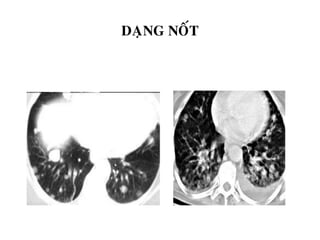

DAÏNG NOÁT

-Tree-in-bud (maàm caây)

-Noát phaân boá ngaãu nhieân

-Do u, vieâm, buïi phoåi…